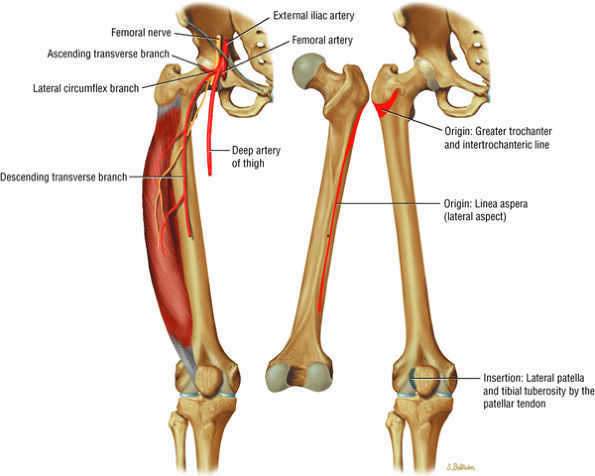

The anterior muscles of the thigh, including the sartorius (Fig. 3.5), the rectus femoris (Fig. 3.6), the vastus lateralis (Fig. 3.7), the vastus medialis (Fig. 3.8), and the vastus intermedius (Fig. 3.9). The vastus lateralis, vastus medialis, vastus intermedius, and rectus femoris are the quadriceps muscles.

FIGURE 3.7 ● VASTUS LATERALIS The vastus lateralis extends the leg and flexes the thigh (hip) and is one of the quadriceps muscles (vastus lateralis, vastus medialis, vastus intermedius, and rectus femoris). Quadriceps muscle fibers are predominantly type II and are adapted for rapid forceful activity. The vastus lateralis obliquus (VLO) fibers of the vastus lateralis muscle interdigitate with the lateral intermuscular septum and insert onto the patella. In a lateral retinacular release, the VLO may be selectively sectioned without involving the main vastus lateralis tendon proper.